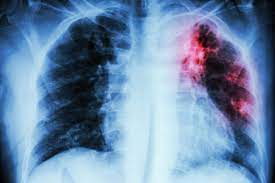

Eventos adversos de enfermedad pulmonar intersticial en hombres con cáncer de próstata que reciben terapia hormonal

Según este análisis de farmacovigilancia de FAERS, no se debe ignorar la asociación entre eventos de EPI y medicamentos de terapia hormonal, incluidos bicalutamida, flutamida, nilutamida, goserelina, degarelix y apalutamida, especialmente en la población japonesa. La función pulmonar de los pacientes con cáncer de próstata debe controlarse cuando reciben los medicamentos de terapia hormonal mencionados anteriormente, especialmente el primer año posterior a la medicación. Br J Clin Pharmacol 29 de marzo de 2022